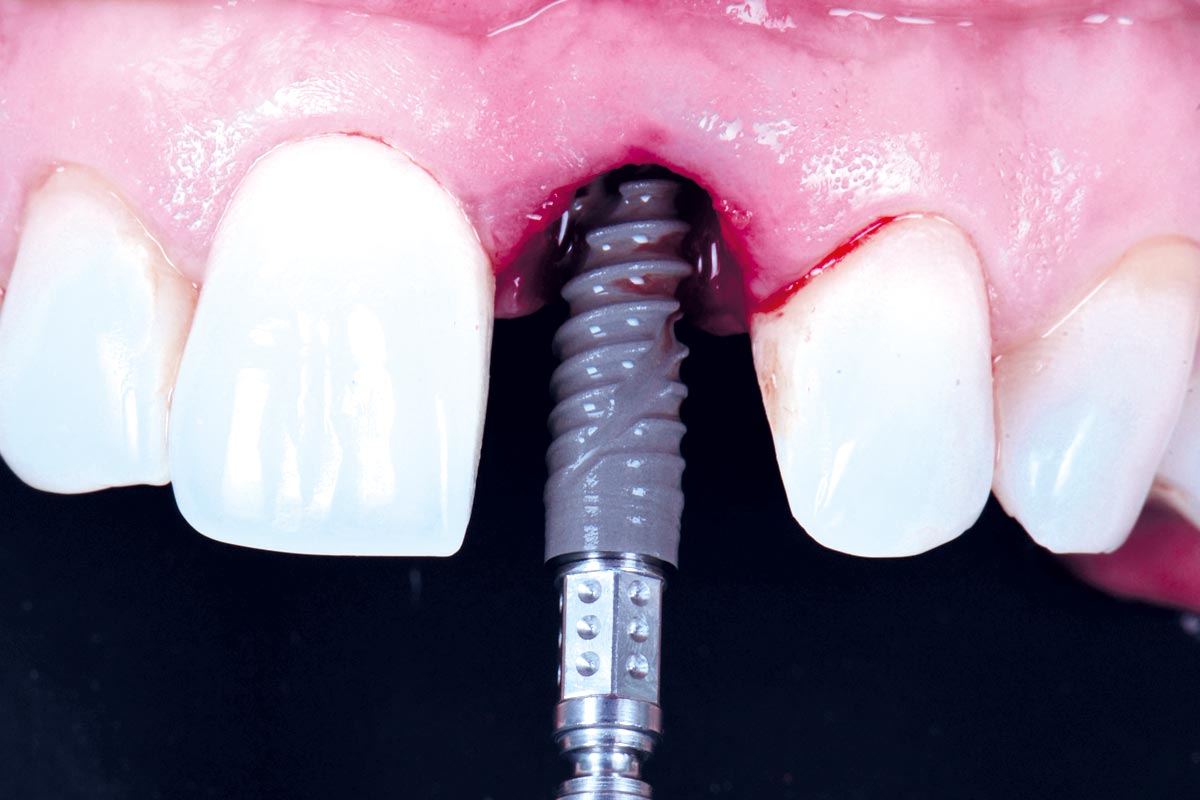

09/30 - Flapless implant placementExcellent aesthetic result of buccal augmentation with mucoderm® and maxgraft® after immediate implant placement - 3-years follow-up - Dr. A. Puišys